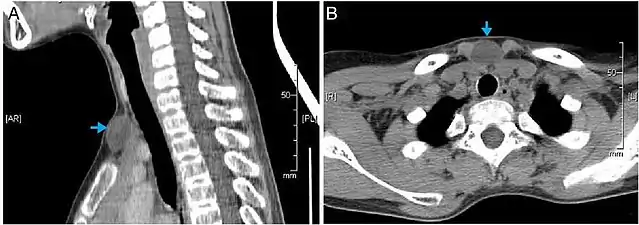

Epidermoid cysts are usually diagnosed when a person notices a bump on their skin and seeks medical attention. The definitive diagnosis is made after excision by a pathologist based on microscopic appearance of a cystic lesion lined by cornified epithelium containing lamellated keratin without calcifications. They can also be seen as isointense lesions on MRI or hyperintensities on FLAIR.